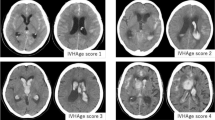

The EVD tract hemorrhage grading scale was used to evaluate the incidence of tract hemorrhage in serial computed tomography scans taken after the procedure4. The scale consists of four grades: grade 0, no tract hemorrhage; grade 1, trace amount of tract hemorrhage; grade 2, tract hemorrhage with moderate intracerebral hematoma without mass effect; and grade 3, large tract hemorrhage with mass effect (Fig. 1). Tract hemorrhage was analyzed as a binary variable, with patients being classified as either having or not having tract hemorrhage.